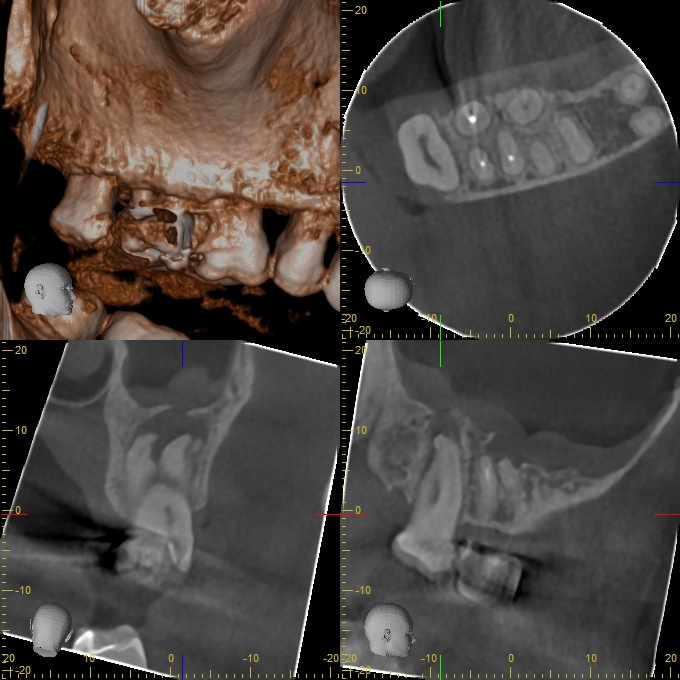

XYZView_20140429_111906

680 × 680

2D vs. 3D (XXVII)